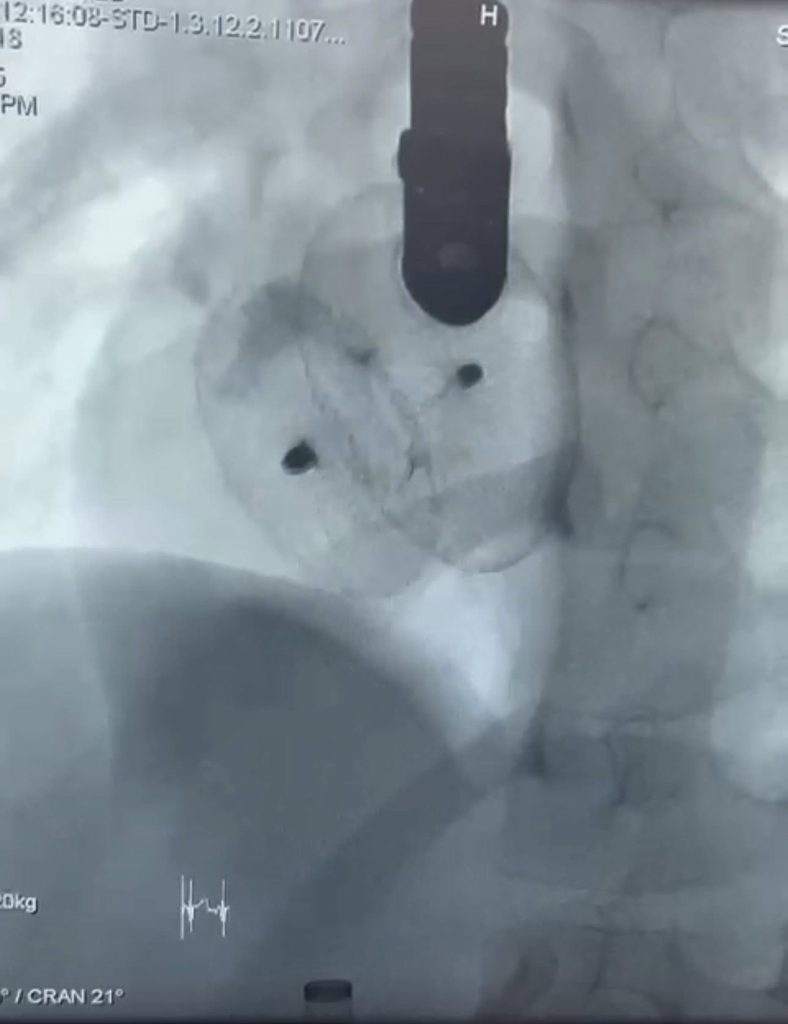

The third scientific conference of tropical medicine and gastroenterology department – Sohag University Hospital